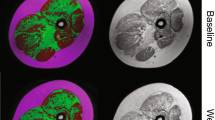

For every patient, regions of interest (ROI) were drawn in thigh muscles (Fig. 1) and care was taken to areas of chemical shift artefact. Three ROIs were chosen to evaluate the knee extensors (quadriceps), knee flexors (hamstrings) and adductor muscle groups. All ROIs were drawn by one co-author (M.S.) and independently checked for quality on raw images and calculated maps by a radiologist with 5 years experience in neuromuscular imaging (A.F.) and by one physicist performing the evaluations (M.G.). All MRI evaluations were performed blinded to clinical status and MFM measurements.

In the two-point Dixon method [13], two images at identical positions are acquired such that water and fat protons are in-phase and opposed-phase, respectively. A combination of these images yields water (w) and fat (f) images. Relative fat content maps were generated from the pixelwise fat fraction given by f/(f + w). ROIs were placed on the maps and the mean fat content was calculated for each muscle group.